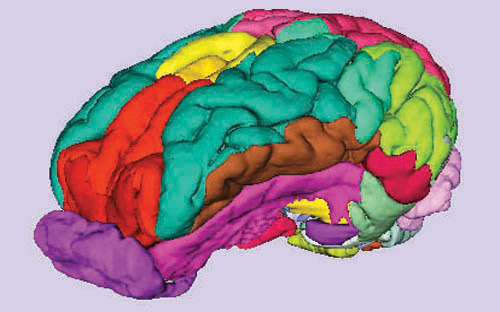

علماء قطعوا مخ امرأة ألمانية إلى 7400 شريحة

علماء قطعوا مخ امرأة ألمانية إلى 7400 شريحة

يوليش - (د ب أ):

صمم علماء، قطعوا مخ امرأة توفيت عن عمر يناهز 65 عاما إلى 7400 شريحة، أطلساً رقمياً ثلاثي الأبعاد للمخ البشري بدقة أوضح 50 مرة من النماذج السابقة الموجودة بالفعل. ونشر المشروع الذي أطلق عليه « بيج برين» في العدد الأخير للدورية الأمريكية للعلوم. ويظهر النموذج خصائص أدق من شعرة الانسان وتقريبا على نطاق الخلايا الفردية، وفقا لما قالته كارتين أمونتس، عالمة الأعصاب في مركز أبحاث يوليش بألمانيا التي تشرف على البحث إنه «على الرغم من أن كل الخلايا لا تزال غير واضحة بشكل كبير، إلا أننا نشاهد كيف أنها مرتبة بصورة مكثفة للغاية وكيفية توزيعها. نكتشف الركن الأبعد في المخ».

وقدمت قياسا على سبيل المثال. وقالت إنه بينما يمكن التعرف على القارات والبلدان والمدن في خرائط المخ القديمة « يمكننا الآن التعرف على شوارع فردية». وقالت إن نموذج المخ يمكن تزويده في وقت لاحق بالبيانات بشأن التركيب الجزيئي والمعلومات الجينية أو الاتصالات بين مناطق الدماغ. ووجد العلماء أن الخلايا مرتبة وفقا لوظائف الدماغ. وقالت أمونتس إن «الترتيب يعتمد على إذا ما كانت المنطقة تسيطر على الحركة أو الأصوات أو الإشارات الضوئية». ويهدف أطلس بيج برين لبنية خلايا المخ إلى تسهيل إلقاء نظرات مقربة مهمة على عمليات مثل الإدراك واللغة والعواطف. كما يرغب العلماء في فهم السبب وراء فشل هذه العمليات أحيانا.

أطلس ثلاثي الأبعاد للمخ !

أطلس ثلاثي الأبعاد للمخ !

برلين - د ب أ

صمم علماء، قطعوا مخ امرأة توفيت عن عمر يناهز 65 عاماً إلى 7400 شريحة أطلس رقمي ثلاثي الأبعاد للمخ البشري بدقة أوضح 50 مرة من النماذج السابقة الموجودة بالفعل.

ونشر المشروع الذي أطلق عليه "بيغ برين" في العدد الأخير للدورية الأمريكية للعلوم.

ويظهر النموذج خصائص أدق من شعرة الإنسان وتقريباً على نطاق الخلايا الفردية، وفقاً لما قالته كارتين أمونتس، عالمة الأعصاب في مركز أبحاث يوليش بألمانيا والأستاذ بجامعة دوسلدورف والتي تشرف على البحث. هاتان المؤسستان إلى جانب مستشفى ومعهد مونتريال للعلوم العصبية، وفرت الجزء الأكبر من فريق البحث.

وقالت أمونتس "إنه على الرغم من أن كل الخلايا لا تزال غير واضحة بشكل كبير، إلا أننا نشاهد كيف أنها مرتبة بصورة مكثفة للغاية وكيفية توزيعها لنكتشف الركن الأبعد في المخ".

وقدمت قياساً على سبيل المثال. وقالت إنه بينما يمكن التعرف على القارات والبلدان والمدن في خرائط المخ القديمة "يمكننا الآن التعرف على شوارع فردية".

وقالت إن نموذج المخ يمكن تزويده في وقت لاحق بالبيانات بشأن التركيب الجزيئي والمعلومات الجينية أو الاتصالات بين مناطق الدماغ.

ووجد العلماء أن الخلايا مرتبة وفقاً لوظائف الدماغ. وقالت أمونتس إن "الترتيب يعتمد على إذا ما كانت المنطقة تسيطر على الحركة أو الأصوات أو الإشارات الضوئية".

ويهدف أطلس بيغ برين لبنية خلايا المخ إلى تسهيل إلقاء نظرات مقربة مهمة على عمليات مثل الإدراك واللغة والعواطف. كما يرغب العلماء في فهم السبب وراء فشل هذه العمليات أحياناً.

وقالت أمونتس إن "بيغ برين" سيساعد الأطباء أيضاً، وأشارت إلى أنه خلال التحفيز الدماغي العميق لمرضى مصابين بداء باركنسنون، على السبيل المثال فإن الموضع الدقيق للموصلات الكهربائية بسمك اثنين مليمتر هو أمر مهم. وأوضحت أن "الخرائط المستخدمة لهذا الغرض غير دقيقة للغاية في أجزاء منها"، مشيرةً إلى أن بيغ برين يمكن أن يستخدم في حالات الاضطرابات العصبية الأخرى.